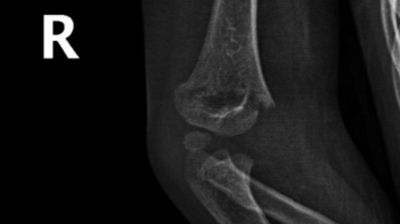

一位4岁小女孩因不慎摔伤导致右肘部肿痛被家长带来我院骨科就诊,经过检查后诊断为“右侧肱骨远端骨折”,因骨折有移位且对位不佳,建议行手术治疗。

骨折部位术前